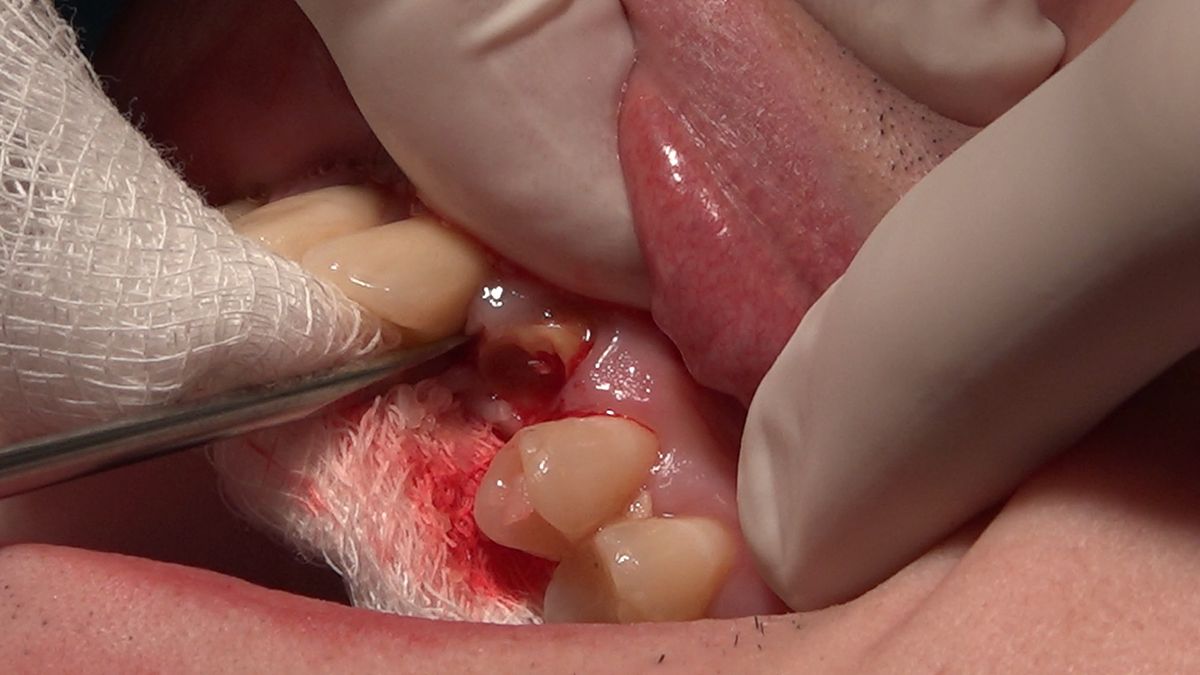

Practiculum Implantologii – Sezon VIIB, sesja 7, dzień 2